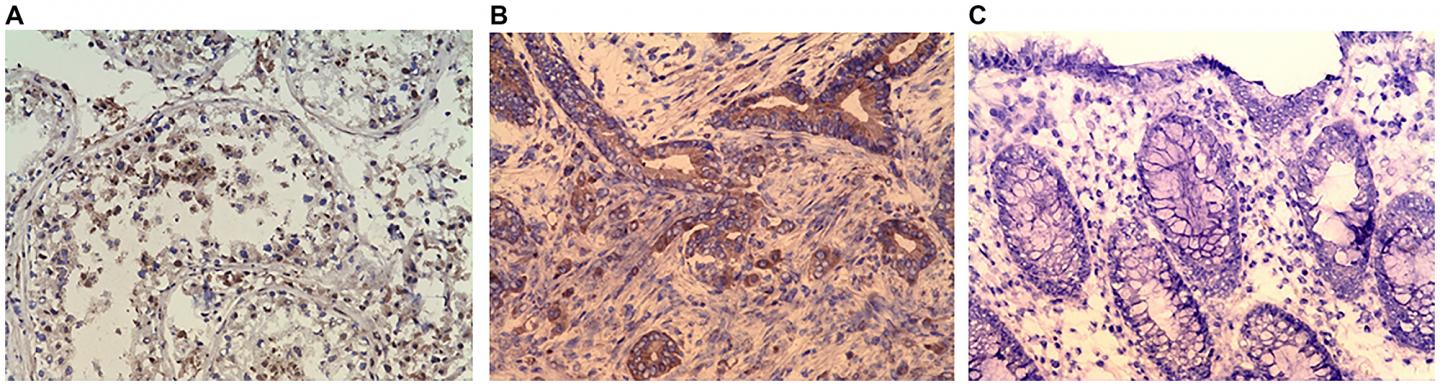

image: (A) Immunohistochemistry (IHC) staining of testis (positive control). (B) IHC staining of colonic adenocarcinoma. (C) IHC stating of Normal colonic mucosa (negative control). Purified rabbit anti-human CABYR polyclonal antibody for CABYR a/b and c antigen isoforms were used in IHC.

Analysis of CABYR protein expressions by immunohistochemistry in tumor and normal colon tissues was also performed.

The percent of patients with a relative expression ratio of malignant to normal tissues over 1 was 70% for CABYR a/b and 72% for CABYR c. The percent with both a M/N ratio over 1 and expression levels over 0.1% of testis was 23.4% for CABYR-a/b and 25.5% for CABYR c. CABYR expression in tumors was further confirmed by immunohistochemistry.

CABYR expression in tumors was further confirmed by immunohistochemistry